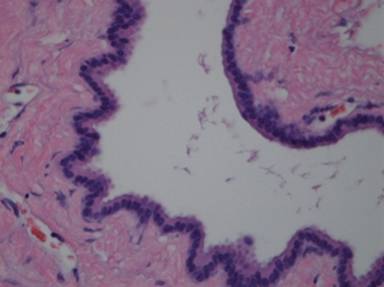

Grossly, the specimen measuring 7x6x3 cm in size was a multiloculated cystic lesion with a thin wall and contained watery clear fluid. No papillary or solid components were seen (Figure 3). Microscopically, the cyst was lined by a single layer of cuboidal cells without stratification or papillary growth (Figure 4).

Figure 4. The epithelium was composed by a single layer of cuboidal cells. |

The lining cells had eosinophilic to basophilic cytoplasm without nuclear atypia, mitosis, or mucinous differentiation. No ovarian-like stroma was seen. Occasional small clusters of residual pancreatic elements including islet cells and acinar glands were also seen in the cystic wall (Figure 5).